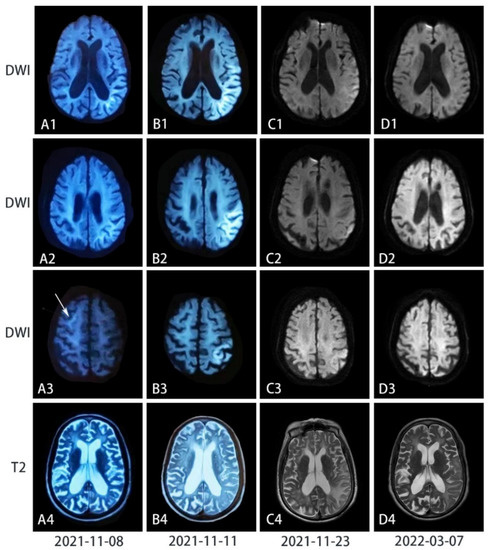

3. Results